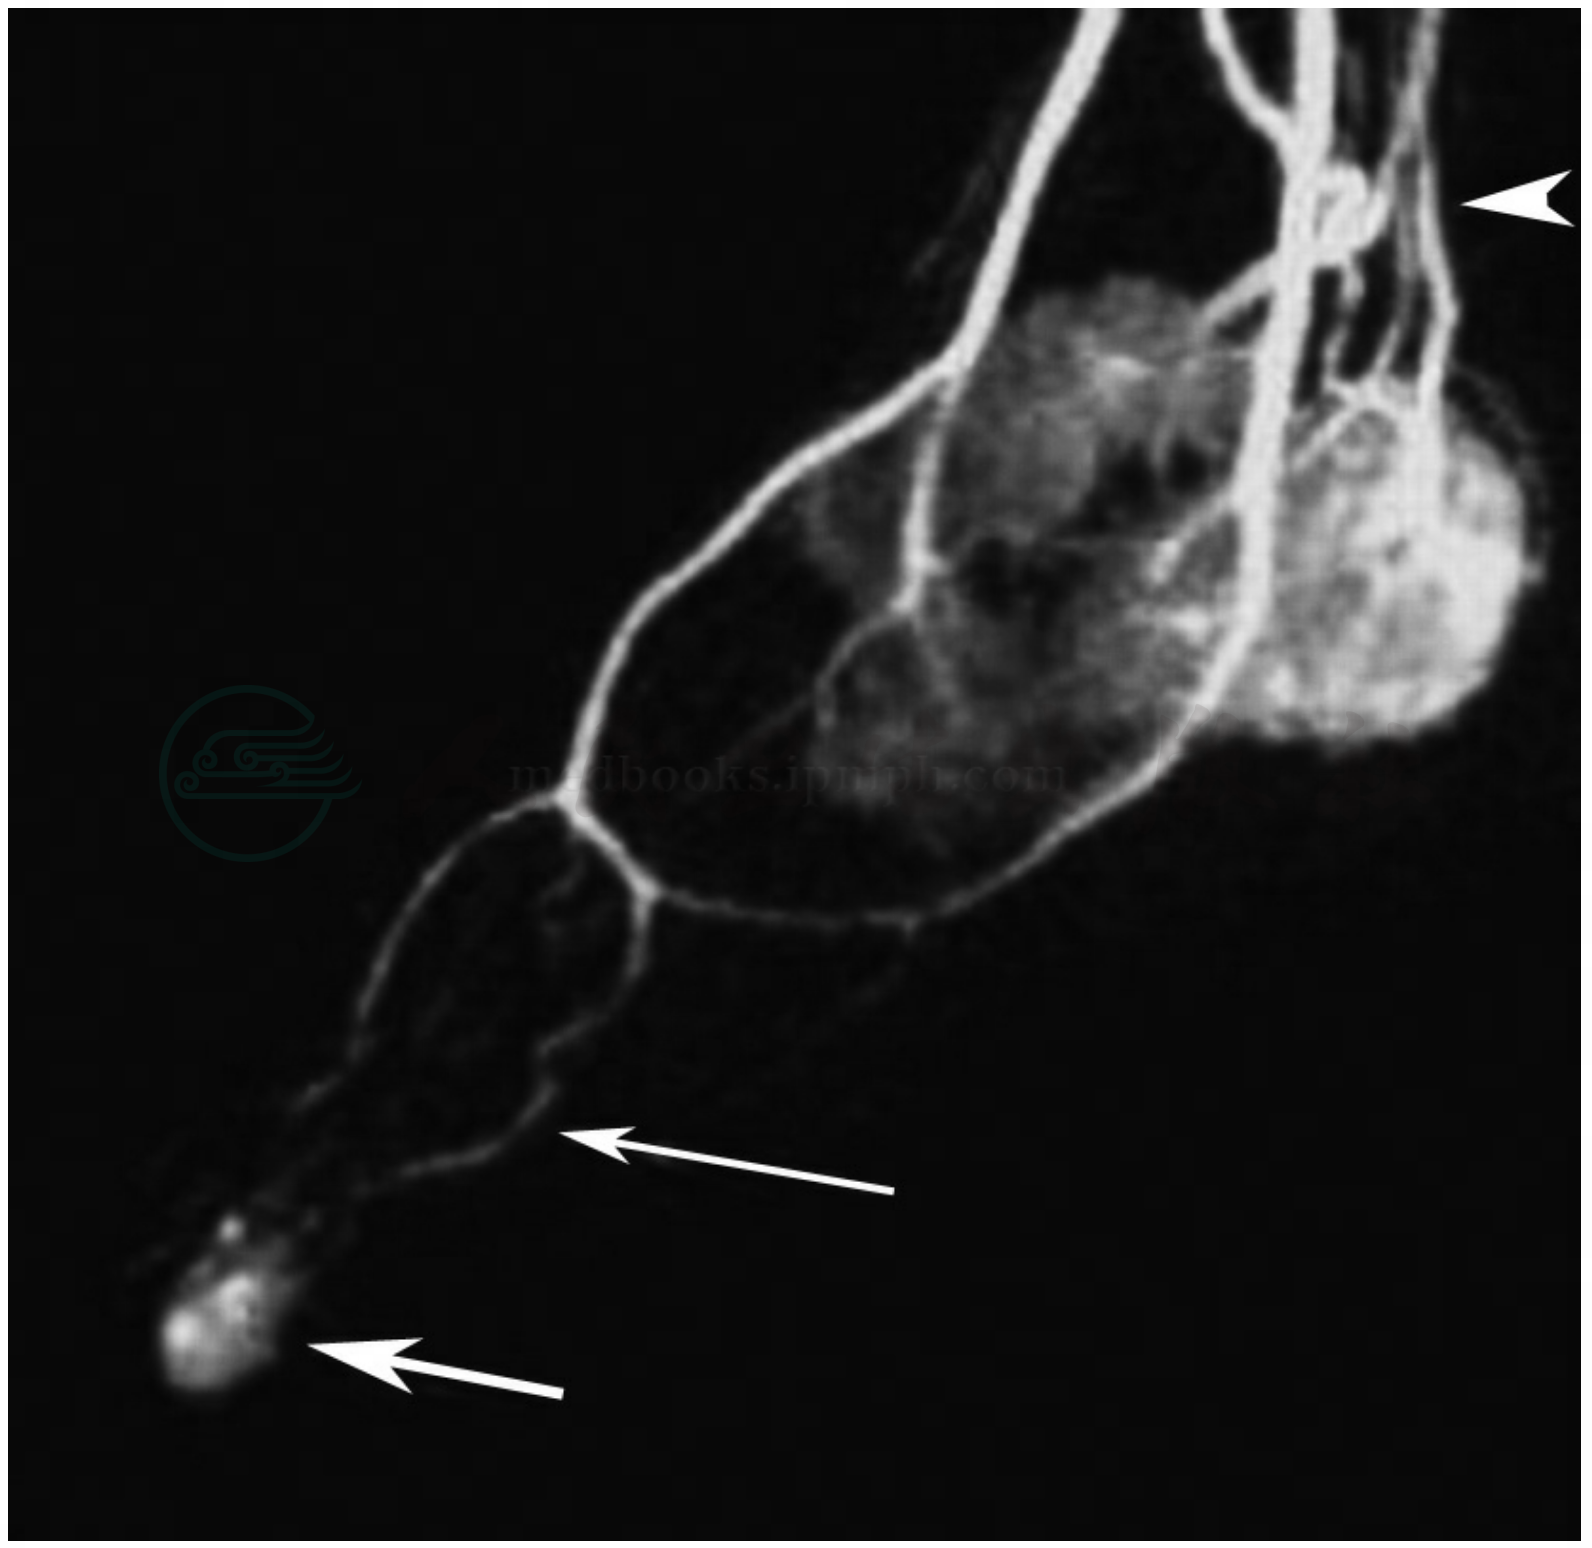

图7 血管瘤三期3D DCEMRA

注:动脉晚期,瘤体信号增强(箭头)。

图8 血管瘤三期3D DCEMRA

注:静脉期,瘤体信号进一步增强,呈亮灯泡状(箭头)。